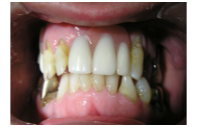

2) Anterior view with denture

2 Ideally treatment option 7 can be completed...

3 Implant supported bridge posteriorly...

The final decisions and treatment considerations would be made following provisional wax up...